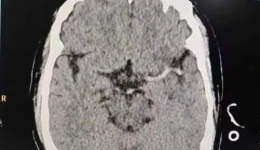

2个星期前,怀孕36+4周的准妈妈钟女士突发脑出血,紧急送到茂名市人民医院,在多学科协作奋力抢救下,这位危重孕产妇从危险边缘拉回,成功挽救了一大一小两条生命。不明原因头痛呕吐竟是脑出血4月18日晚上,钟女士在家洗头后不久,突然觉得右侧头痛...